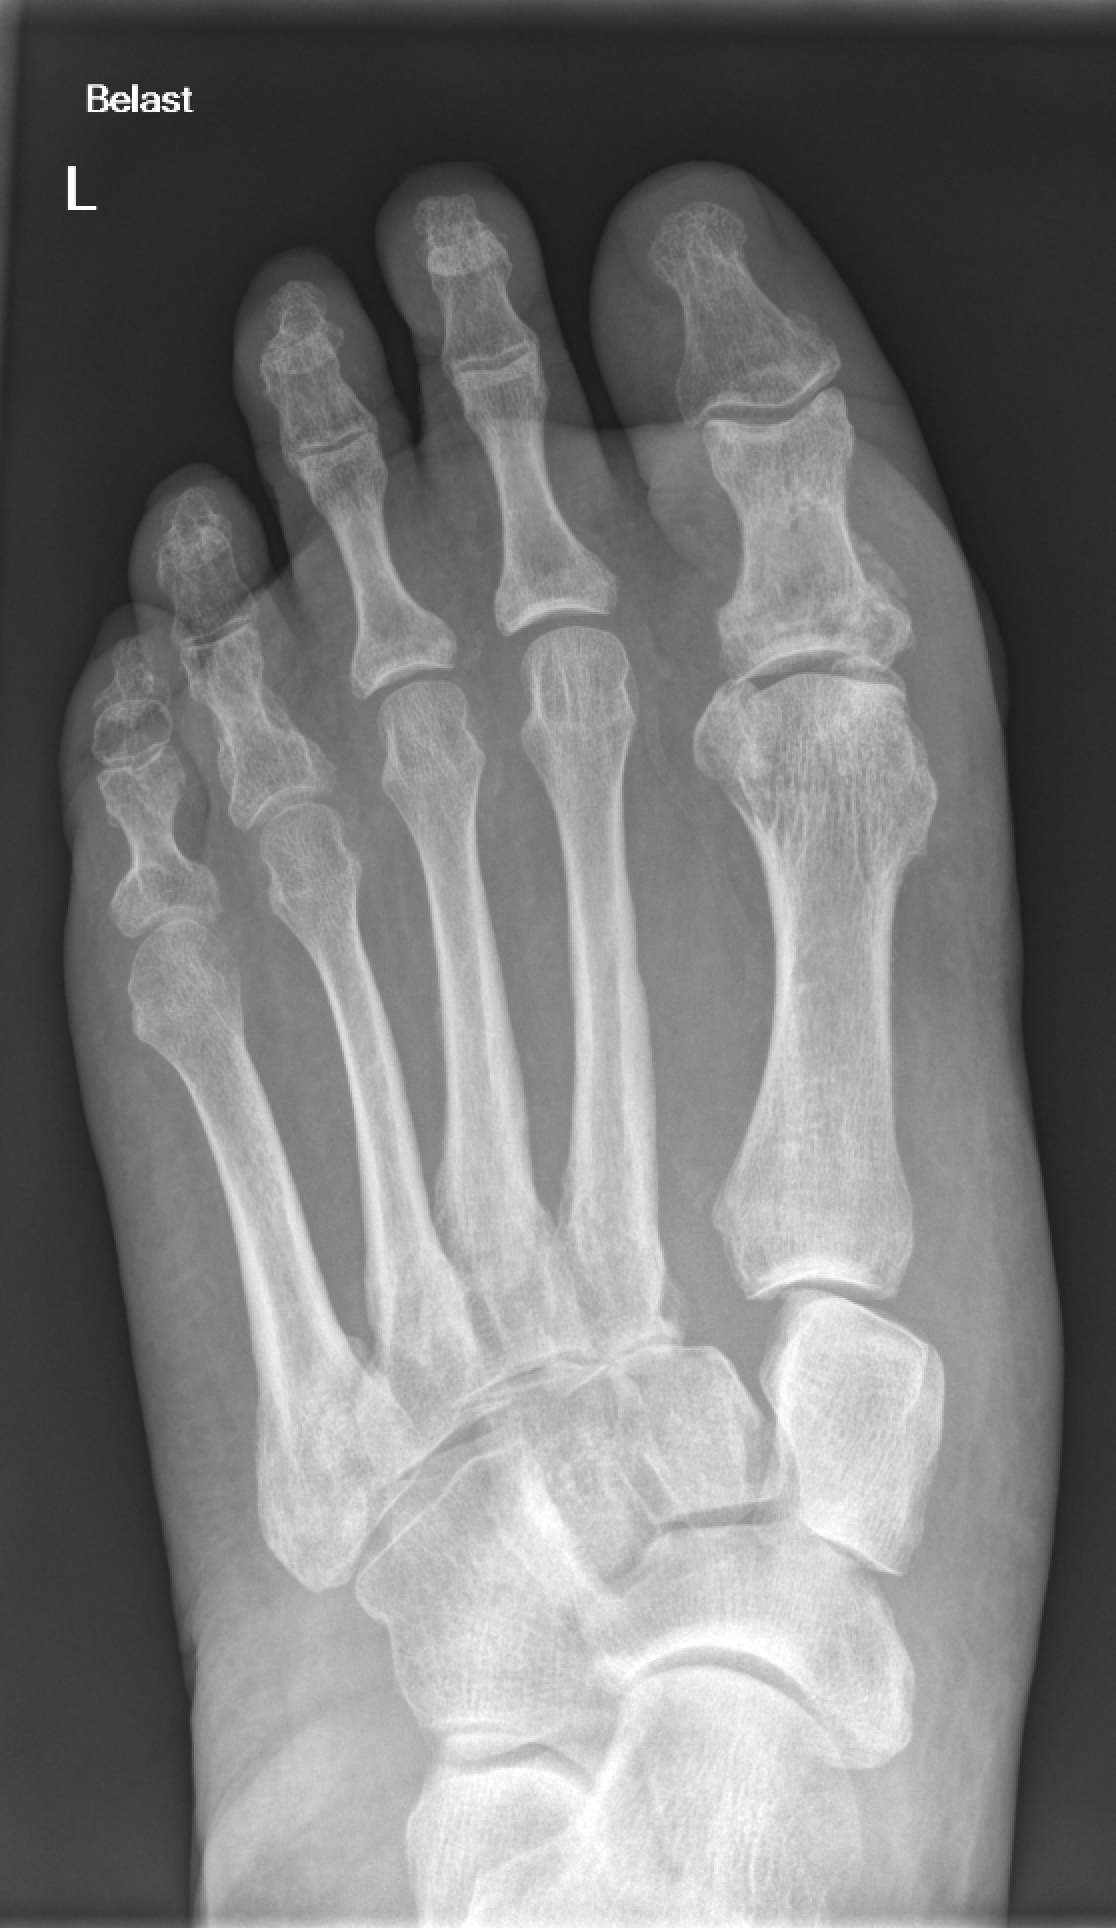

De klinische implicatie De belangrijkste en vaak gemiste diagnose in het Lisfranc gewricht is een fractuur. Zowel na laag- als hoogenergetisch letsel kan dit letsel optreden. De meest overzichtelijke classificatie is die van Quenu: unidirectionele verplaatsing van 1 of enkele (vaak 1 en 2) metatarsale, homolaterale (vaak lateraal, soms mediaal) verplaatsing van alle metatarsale en divergerende verplaatsing (welke combinatie dan ook) van alle metatarsale in meerdere richtingen (lateraal en dorsaal, of mediaal en lateraal, et cetera). De diagnose wordt vaak gesteld op een belaste röntgenopname van de voet of een CT. Conservatieve behandeling heeft alleen plaats bij niet verplaatste en stabiele fracturen. Stabiliteit kan met een stress opname of open (onder narcose) testen worden bepaald. Of de benodigde fixatie tijdelijk of meteen een artrodese moet zijn, is niet duidelijk. Ook variëren de beschreven methoden van fixatie met k-draden tot platen of schroeven of zelfs een endo-button.3